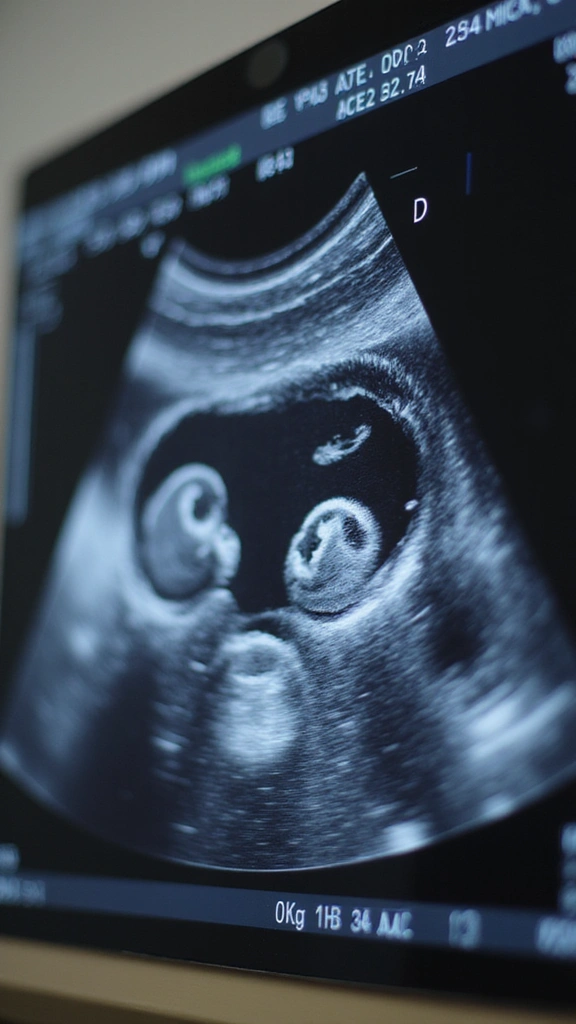

Amazon$9.992. Twin-to-Twin Transfusion Syndrome (TTTS)

TTTS is a worry for parents carrying identical twins. It happens when the twins share blood vessels in the placenta and the flow becomes uneven. One baby may get too much blood and the heart works hard. The other may get too little and grow slowly. Early ultrasound catches TTTS before it harms them. In cases, doctors monitor closely. If needed, a procedure can balance blood flow.

– Schedule ultrasounds during pregnancy.

– Talk with your doctor about TTTS signs and how to spot them.

Being informed helps you act fast and protect both babies.